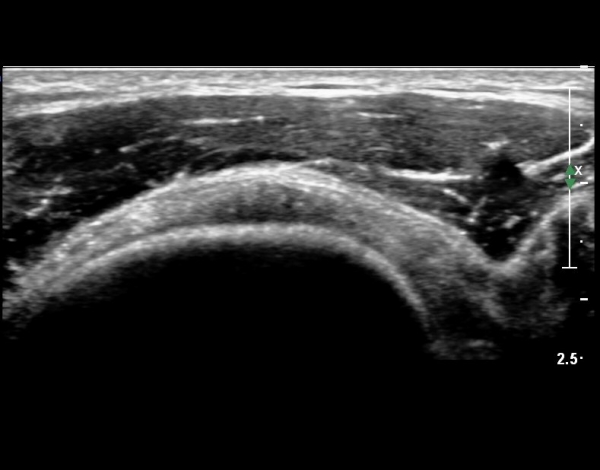

°ß°©ÇÏ±Ù°Ç Á¾´Ü¸ç°Ë»ç¿¡¼­ °Ç »óºÎ¿¡ ÀÌÁúÀûÀÎ ¿¡ÄÚ¸¦ º¸¿© °ß°©ÇÏ±Ù°Ç »óºÎ ºÎºÐÆÄ¿­ÀÌ ÃßÁ¤µÈ´Ù(»çÁø 3),

°ß°©ÇÏ±Ù°Ç ÇϺο¡¼­´Â ÀÌ»ó ¼Ò°ßÀÌ °üÂûµÇÁö ¾Ê´Â´Ù(»çÁø 4).